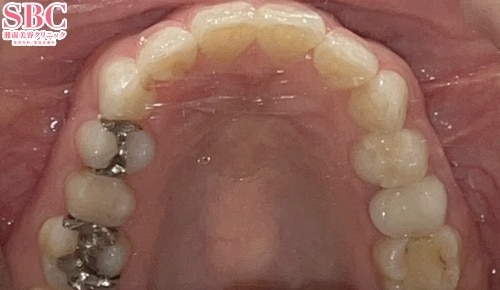

施術後12ヶ月後

段差も重なりも改善されました★

前歯2本が少し出てます・・・

しっかりアーチに入りました★

上下の段差が気になるとのことで、インビザラインGoで矯正治療をした症例になります。

歯の重なりや段差、ねじれがあると磨き残しが起こりやすくなりその結果虫歯や歯周病になりやすくなってしまいます。

並びを改善することで今後の歯の健康を維持することに繋がります★